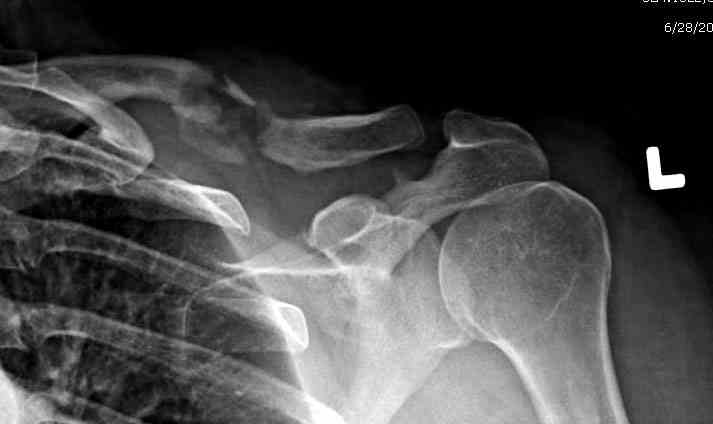

Консервативное лечение, через 8 мес. операция Rockwood pin с костной пластикой в нашем городе другим врачом. После 8 недели падение, гвоздь удален оперирующим хирургом, больная направлена к нам. Фиксация реконструктивной пластиной с трикортикальным графтом, добавлен BMP-2. Для стабилизации фиксацию провели через акромион.

Вот уже два месяца больная также продолжает жаловаться на боли, буквально на днях удалили акромиальную часть пластины с специальной пилой с алмазным покрытием для медицинского металла. До сих пор судьба ложного сустава неизвестна....